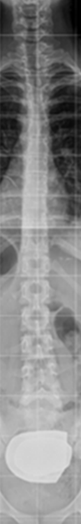

La escoliosis puede presentar una o varias curvas y en su evolución, no mejora (Figura 8). Por eso, se hace imprescindible su seguimiento con sucesivas telerradiografías, lo cual obliga, éticamente, a optimizar su estudio8.

Figura 8. Telerradiografía de escoliosis de una paciente a lo largo del tiempo. Mostrar/ocultar

La localización de estas curvas puede ser torácica, lumbar, o toraco-lumbar. Normalmente existe una, la llamada curva principal, sobre la que asienta la mayor deformidad rotacional. Recordemos que la escoliosis es una deformidad tridimensional en la que el raquis gira sobre sí mismo. Generalmente se acompaña de otra curva llamada secundaria a la primera en un intento de equilibrar en conjunto la columna.